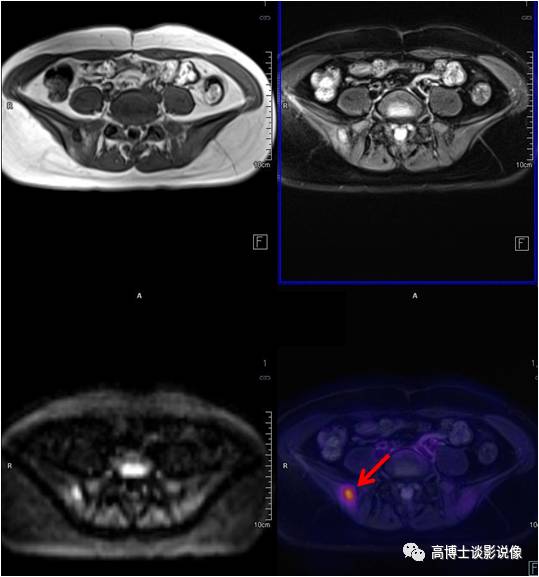

膀胱癌

老年男性,排尿中断半年余,无血尿。膀胱左后壁局限性增厚,病灶以宽基底与膀胱壁相连,长径约1.8cm。膀胱镜证实为膀胱癌。

点评

膀胱癌是泌尿系统最常见的恶性肿瘤,较为明确的两大致病危险因素是吸烟和职业接触芳香胺类物质。绝大多数的膀胱癌患者最初的临床表现是血尿。本例患者无血尿症状,经PET/MR检查偶然发现了膀胱内占位病变。